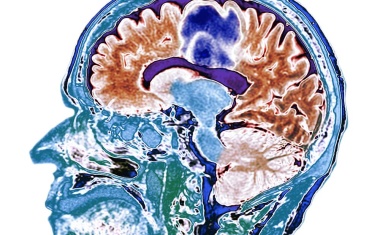

Gehirnnetzwerk zur Behandlung der Parkinson-Krankheit

Die tiefe Hirnstimulation ist ein entscheidendes Verfahren zur Behandlung von Parkinson. Forscher konnten nun das optimale Zielnetzwerk im menschlichen Gehirn identifizieren.

Wissenschaftler der Sektion für Bewegungsstörungen und Neurostimulation der Klinik und Poliklinik für Neurologie der Universitätsmedizin Mainz haben eine wesentliche neue Erkenntnis zur Funktionsweise des Gehirns erzielt.